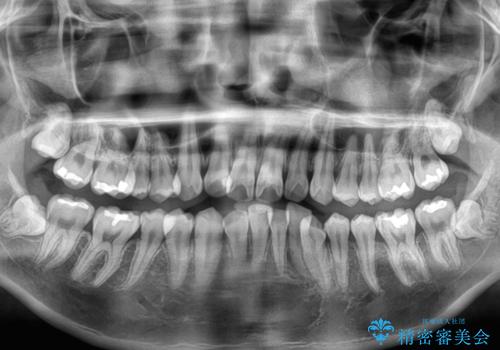

- 全顎的なデコボコを気にして来院された患者様です。

特に前歯のデコボコが顕著であり、上下左右第一小臼歯の4本を抜歯し、ワイヤー装置を使用して咬み合わせ高さを改善しながら、歯列を整えて行くこととしました。